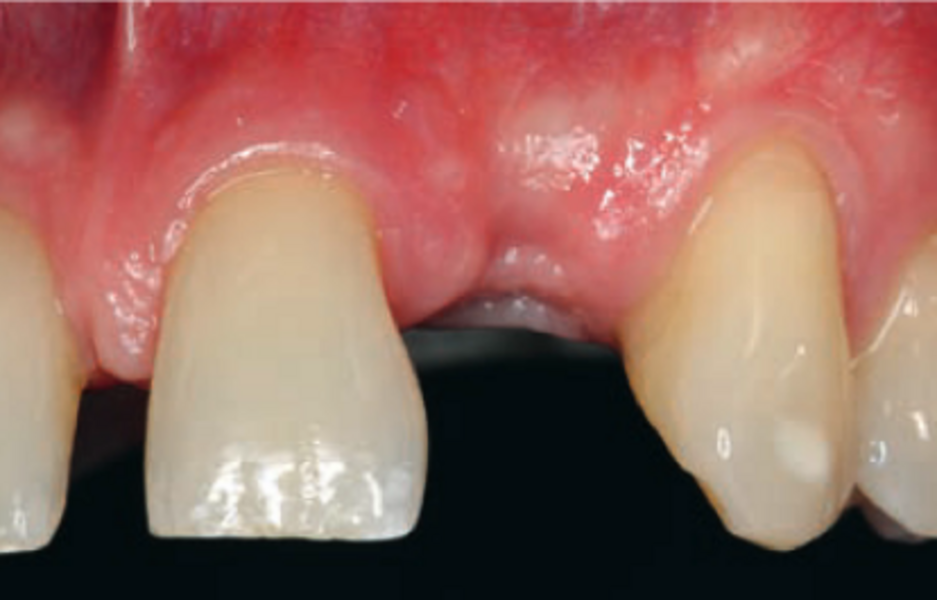

Ein eindrücklicher Case Report ist in der Quintessenz Zahnmedizin publiziert: Der Erhalt der ursprünglichen Gewebearchitektur in der ästhetischen Zone ist eine zentrale Herausforderung in der modernen, zahnärztlichen Implantologie. Wenn die Voraussetzungen für eine Sofortimplantation mit einer prothetischen Sofortversorgung gegeben sind, ist dies ein möglicher Weg die ursprüngliche Morphologie der Hart- und Weichgewebe weitgehend zu erhalten. Der vorliegende Beitrag definiert die Begriffe Sofortimplantation, Sofortversorgung sowie Sofortbelastung und illustriert einen klinischen Fall bei dem nach Fraktur eines Frontzahnes eine Sofortimplantation mit provisorischen Sofortversorgung realisiert werden konnte.

Zeitschrift: Quintessenz Zahnmedizin

Ausgabe: 11/2022, S. 1028 - 1036

Autoren: Dr. Christopher Prechtl, PD Dr. Daniel Hellmann, Dr. Dr. Hans Ulrich Brauer, M.A., M.Sc.